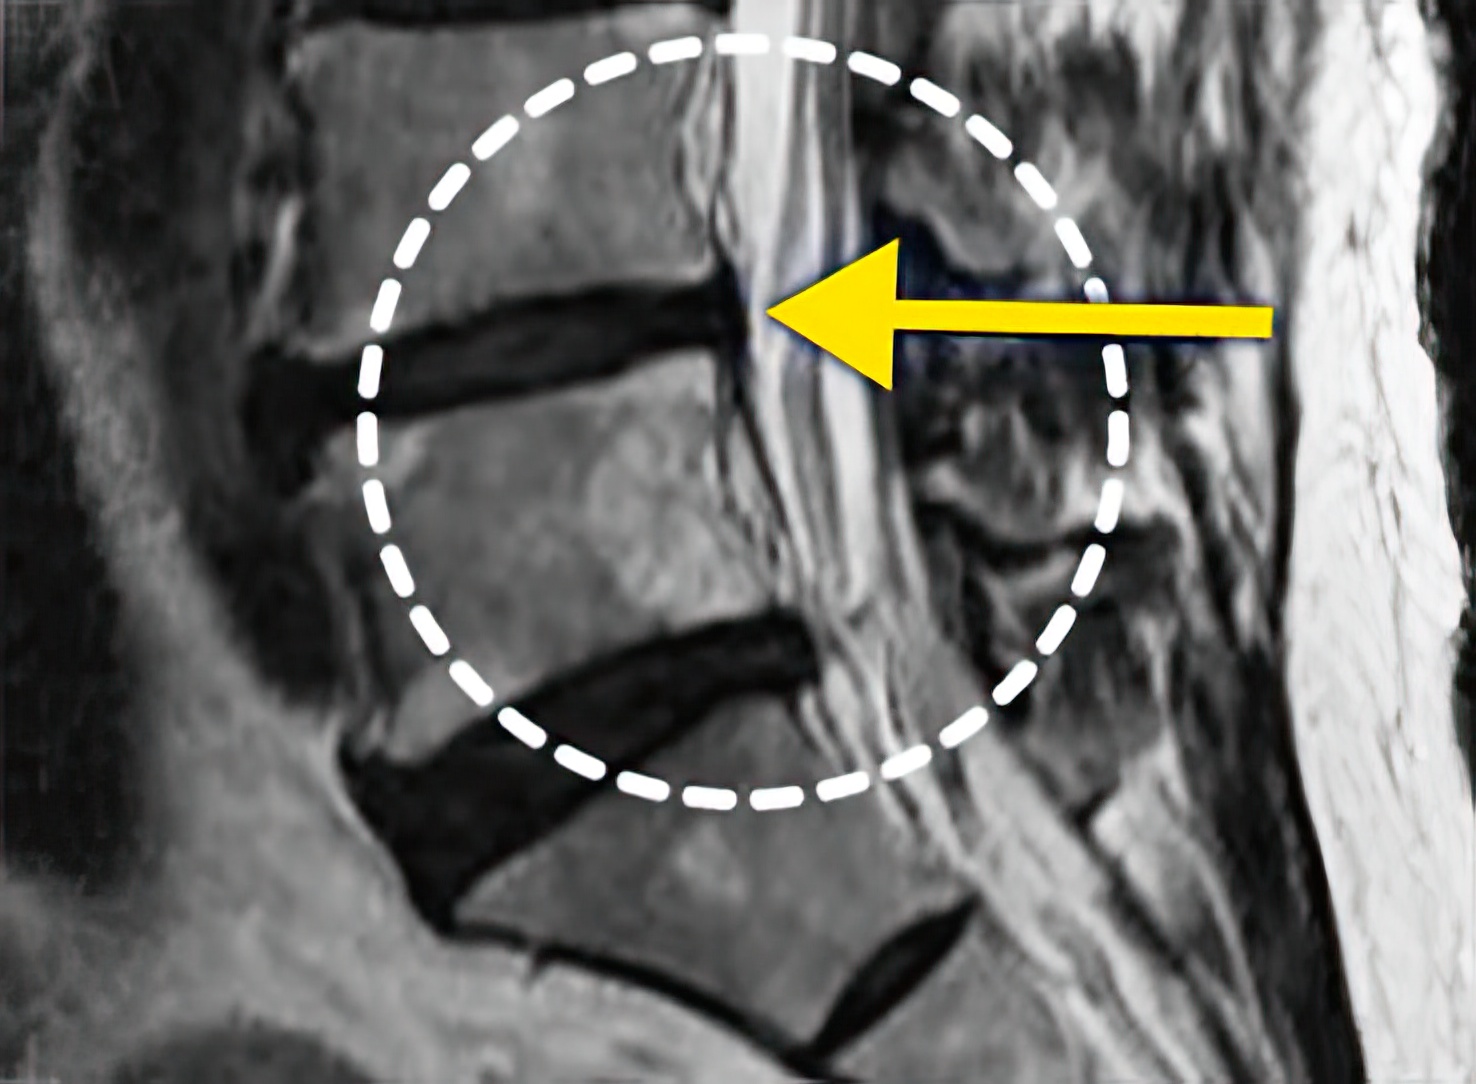

자생 비수술 한방통합치료 후

터진디스크가 흡수된 모습

비수술 치료만으로

터진 디스크 흡수

튀어나온 디스크 대비,

터진 디스크 치료 효과 우수

디스크 흘러내린 정도가

심할수록 흡수 가능성 증가